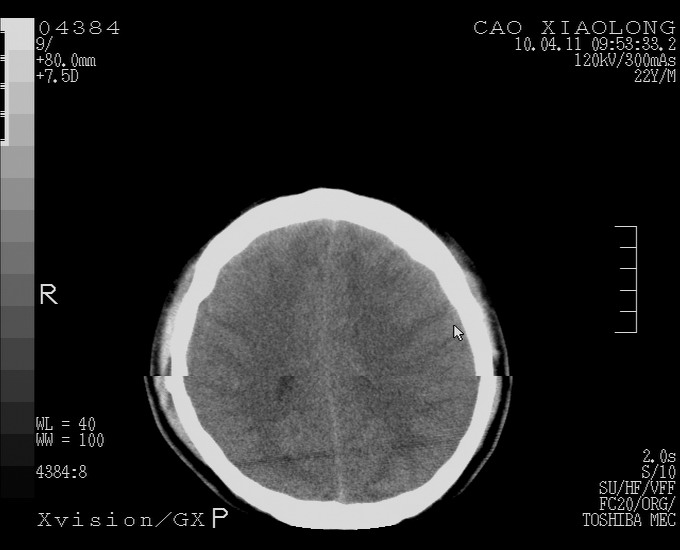

以下是引用随光逐影在2010-4-11 11:00:00的发言:[br]1)左侧额颞顶部硬膜下血肿。2)蛛网膜下腔出血。3)右侧颞顶部颅骨线形骨折。[br][br]20小时后复查:左侧额颞叶脑挫裂伤;左侧额颞顶部硬膜下血肿及蛛网膜下腔出血有吸收表现;右侧颞顶部颅骨线形骨折。[br]